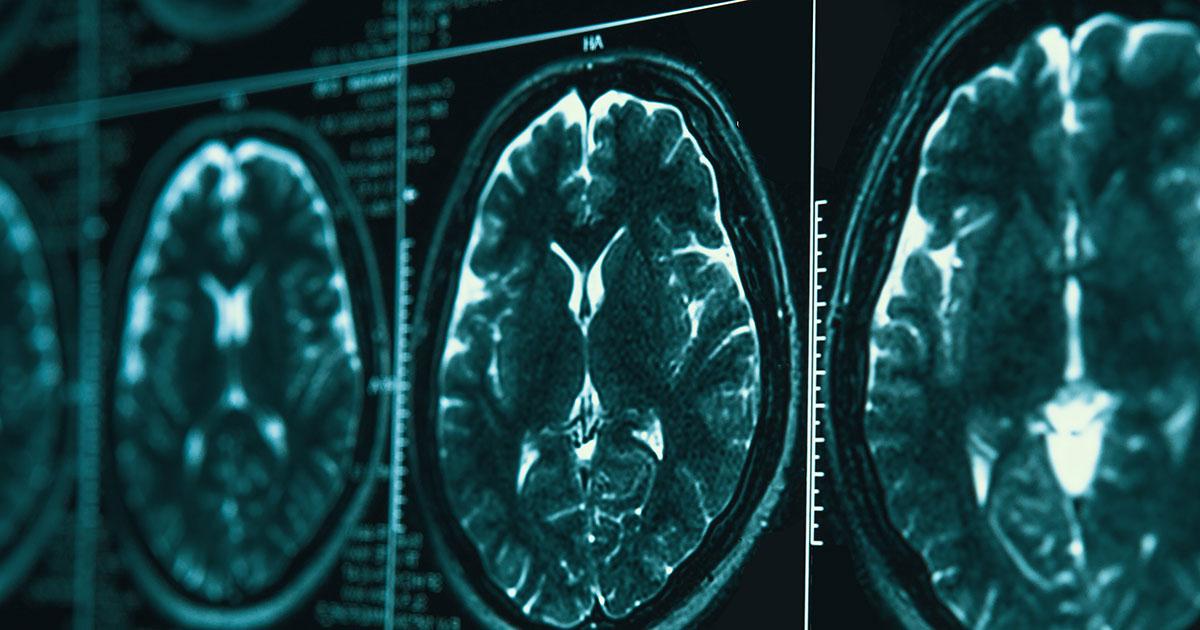

Adriano Aguzzi (University of Zurich, Switzerland), ospite dell’incontro, parla di prioni umani e malattie del cervello.